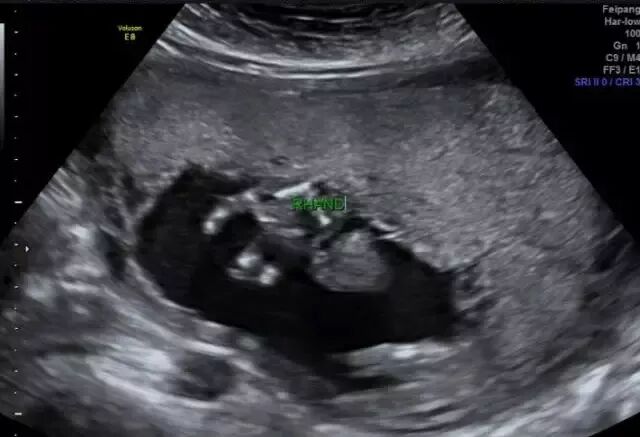

27岁的小美(化名)和相爱多年的男友结婚一年后,一个小生命的悄然到来,给整个大家庭送上了一份惊喜,他们俩感觉太幸福了。然而不幸的事情发生了:小美孕25周四维彩超检查发现胎儿下肢无双腿,双下肢合并外形似鱼尾状,据医生了解,这是一种非常罕见的多发性畸形,双下肢合并外形似鱼尾状,俗称“美人鱼综合症”。

无独有偶,一位40岁的二胎妈妈在一次常规的产检中,发现胎儿下肢是两个大腿骨, 并行排列 ,小腿骨好像有点交叉 。医生介绍正常胎儿的下肢是不停地在妈妈肚子里动的, 呈现一个外八字,像这种情况,医生从医40年也是第一次见,后来确诊为美人鱼综合症。因为多数患病的新生儿出生后,只能存活几个小时,就算活下来,也要接受多次手术治疗。最终,在医院的帮助下,这位二胎妈妈选择了终止妊娠。